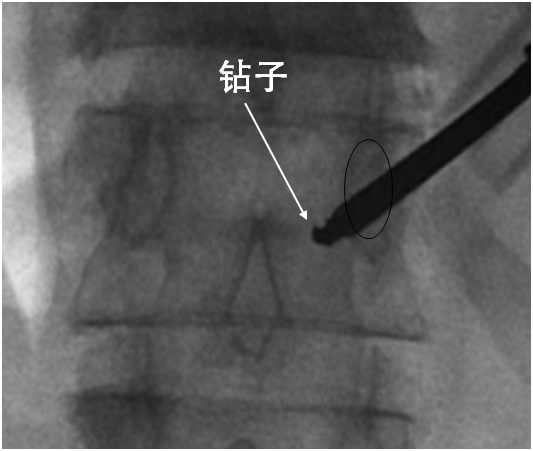

使用钻子开通道。

侧位相钻子直至椎体前中1/2交界处,正位钻头尖位于椎弓根影与棘突连线中点。

钻子必须出外鞘前端2cm,保证球囊完全进入椎体。

侧位像钻头尖在距椎体前缘2mm处停止正位显示钻头尖位于棘突边缘。